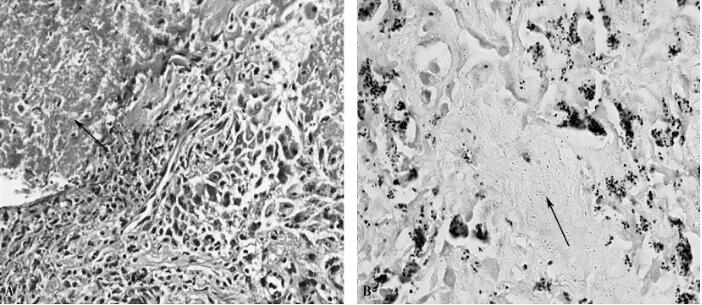

住院第28日复查心脏彩超示左心室血栓消失(图3),第29日CT引导下经皮肺穿刺活检病理结果回报:小灶型干酪样坏死组织,周围包裹上皮样细胞、多核巨细胞,伴间质、纤维组织增生,慢性炎性细胞浸润。抗酸染色找到抗酸杆菌(见图4)。

图4 肺活检病理

A.干酪样坏死(箭头所示);B.抗酸杆菌(箭头所示)